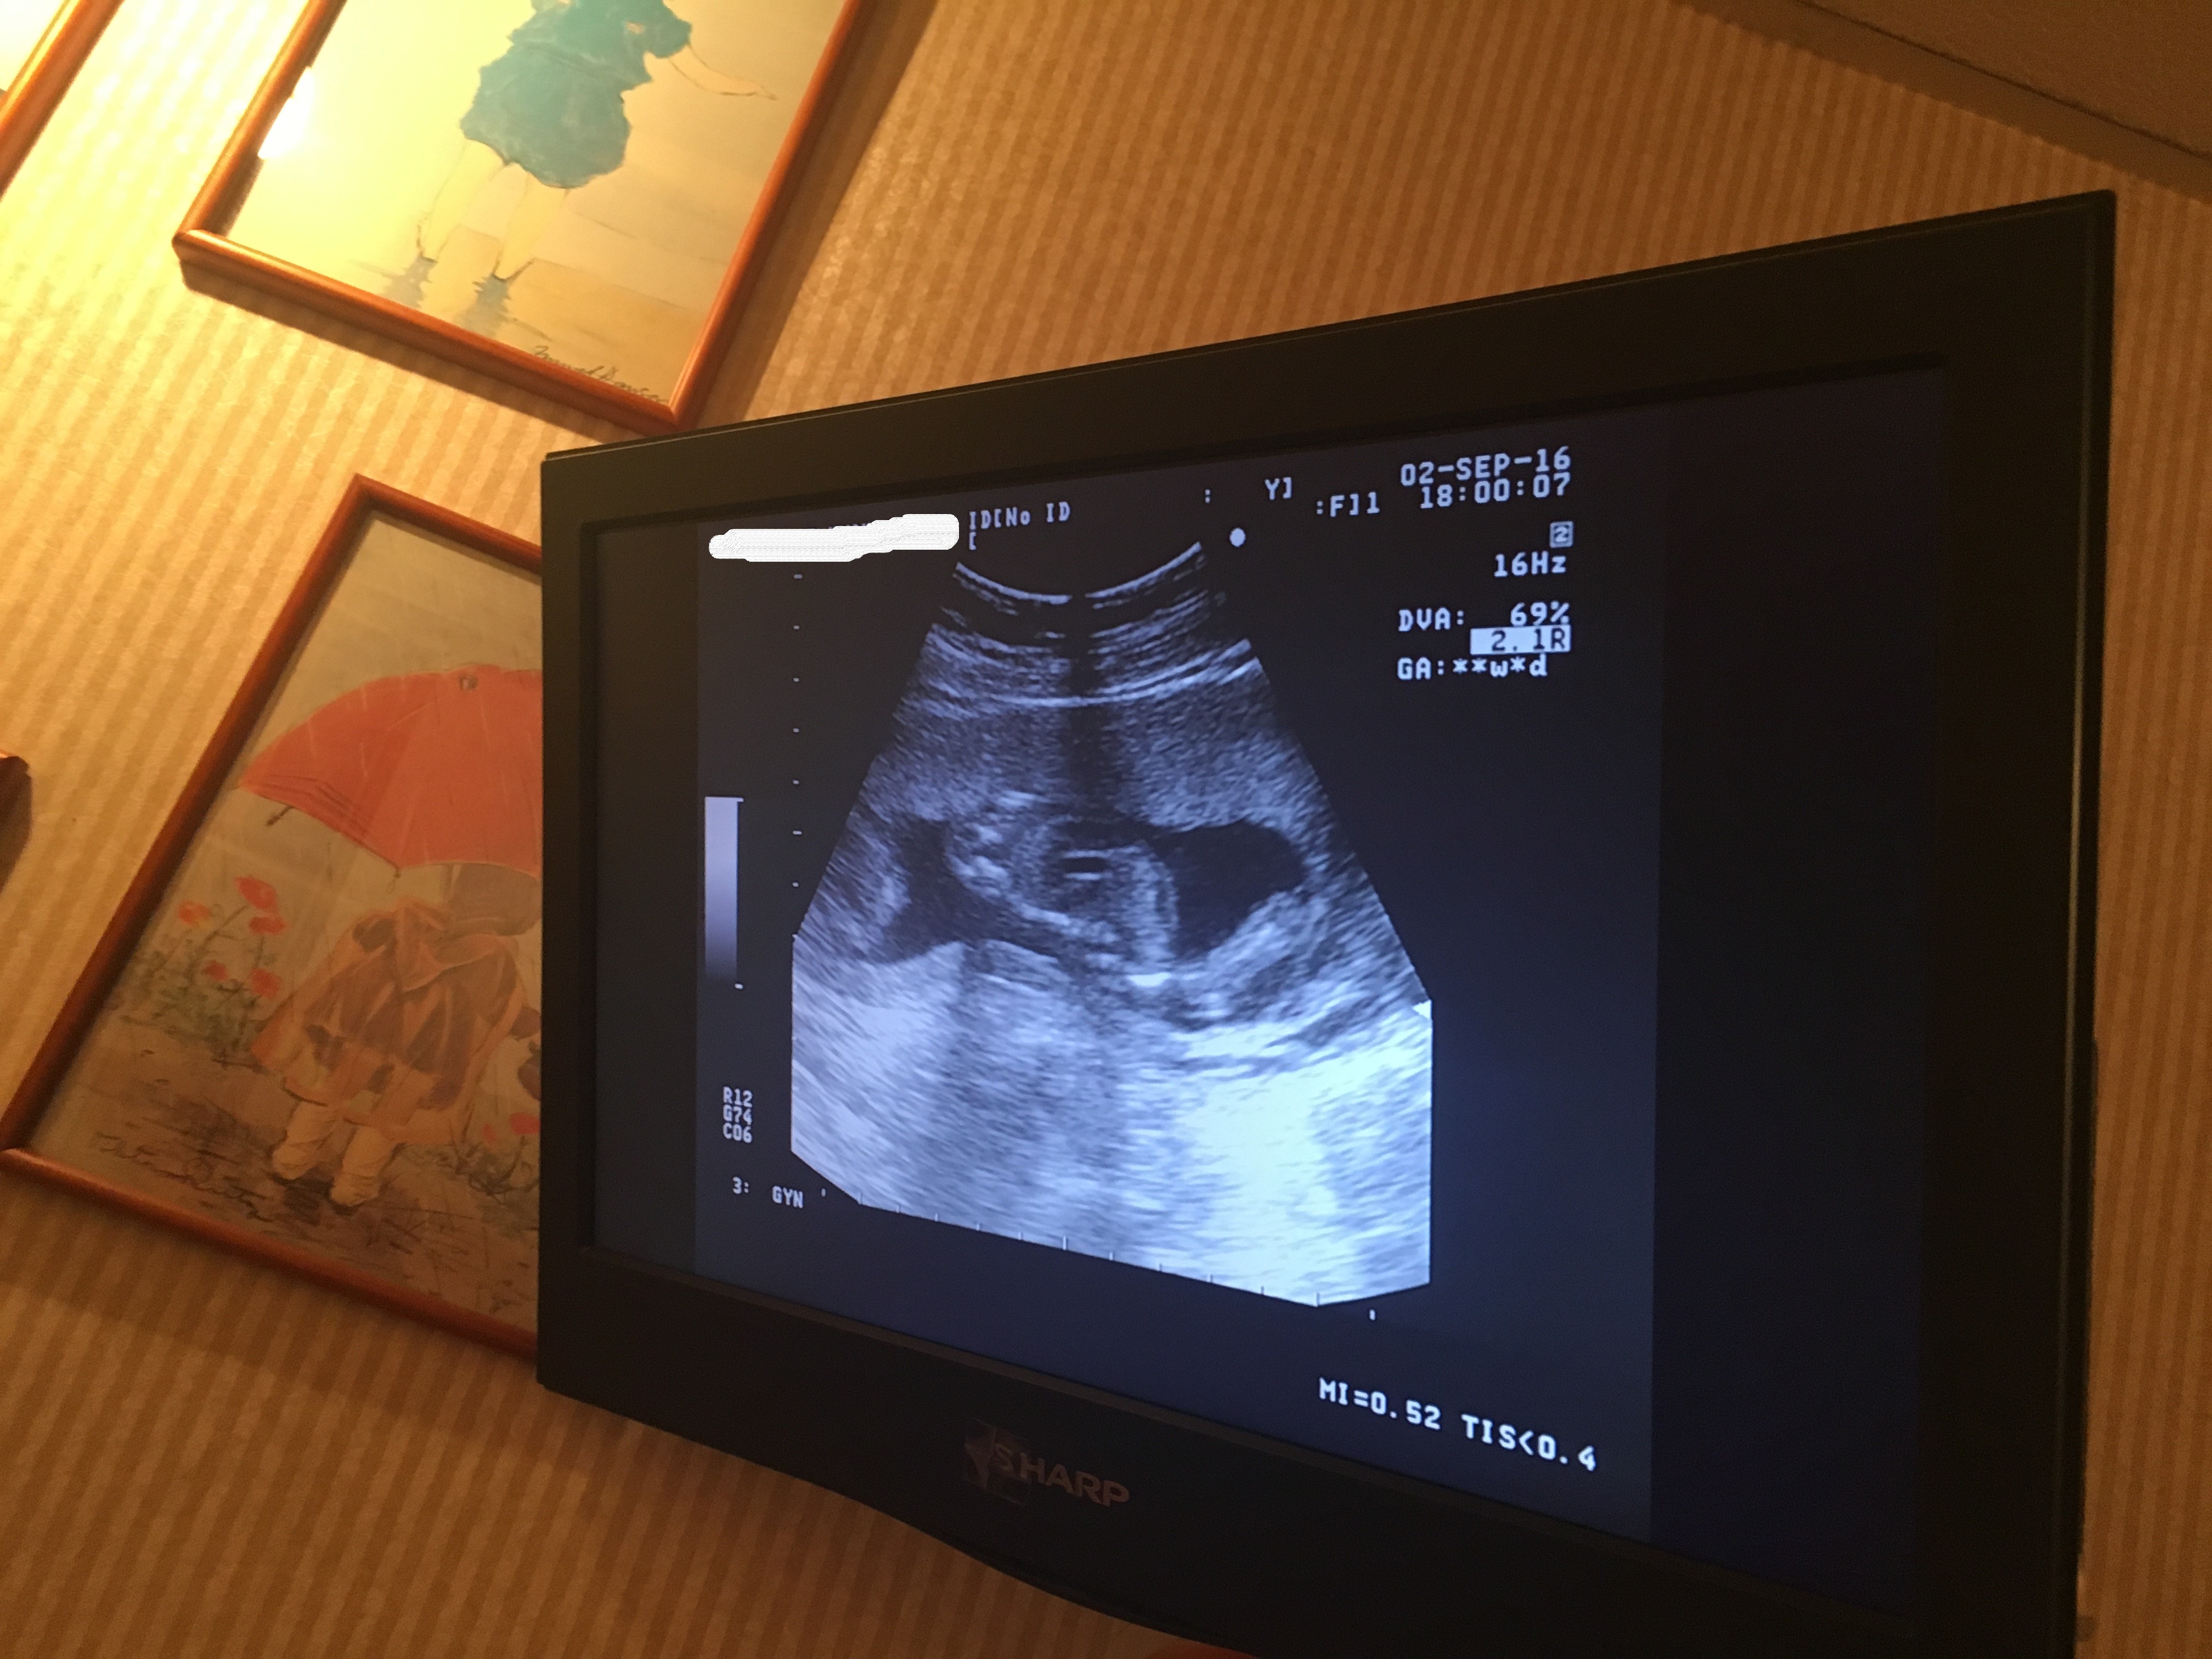

由於醫生在此階段都不能確定原因,唯有寫轉介信回政府醫院作詳細的檢查,結果要等一星期才能到醫院照超聲波,這一個星期極度難捱,一方面擔心BB,另一方面又諗如果真係有事點算?!返醫院照完之後,結果亦顯示BB的腦室是偏大了,醫生建議抽羊水進行化驗,以了解BB的身體有沒有其他問題,別無他法而又時間緊迫的情況之下,我們亦只好接受帶有風險的抽羊水檢查。(聽到都真係心都實埋,抽羊水又好鬼驚)

可幸的是之後幾次再做檢查,都發現丸B的腦室有變細,更加所有生長都正常,回想起嚟真係唔容易,特別係抽羊水呢個經歷,記得嗰朝去到醫院真係好驚,好彩老公可以陪住我抽,而醫生都真係非常細心,照住超聲波睇住BB嘅位置,如果唔係成支針拮入去肚入面都真係幾驚呀!